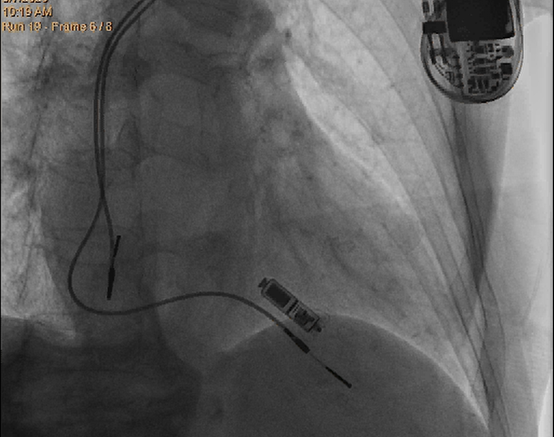

在分析了患者情况和充分考虑患者及其家属意愿后,攀枝花学院附属医院罗晓鸣教授和团队专家们为患者量身定制了缜密的手术方案,采用最新一代Micra AV无导线起搏器进行植入。这款起搏器无需植入电极导线,也无需在胸前皮下制作囊袋,解决了患者担心手术影响外观、感染风险大等忧虑。Micra AV无导线起搏器手术直接植入在心腔内,无伤疤、无切口,患者在植入后几乎感觉不到起搏器的存在,很大程度上提升了患者的治疗体验。

Micra AV无导线起搏器的手术在非全身麻醉下进行,通过股静脉穿刺,将起搏器通过导管植入到心腔内部,手术时间仅有50分钟,患者术后反应良好,预计五天后即可恢复正常的工作和生活。